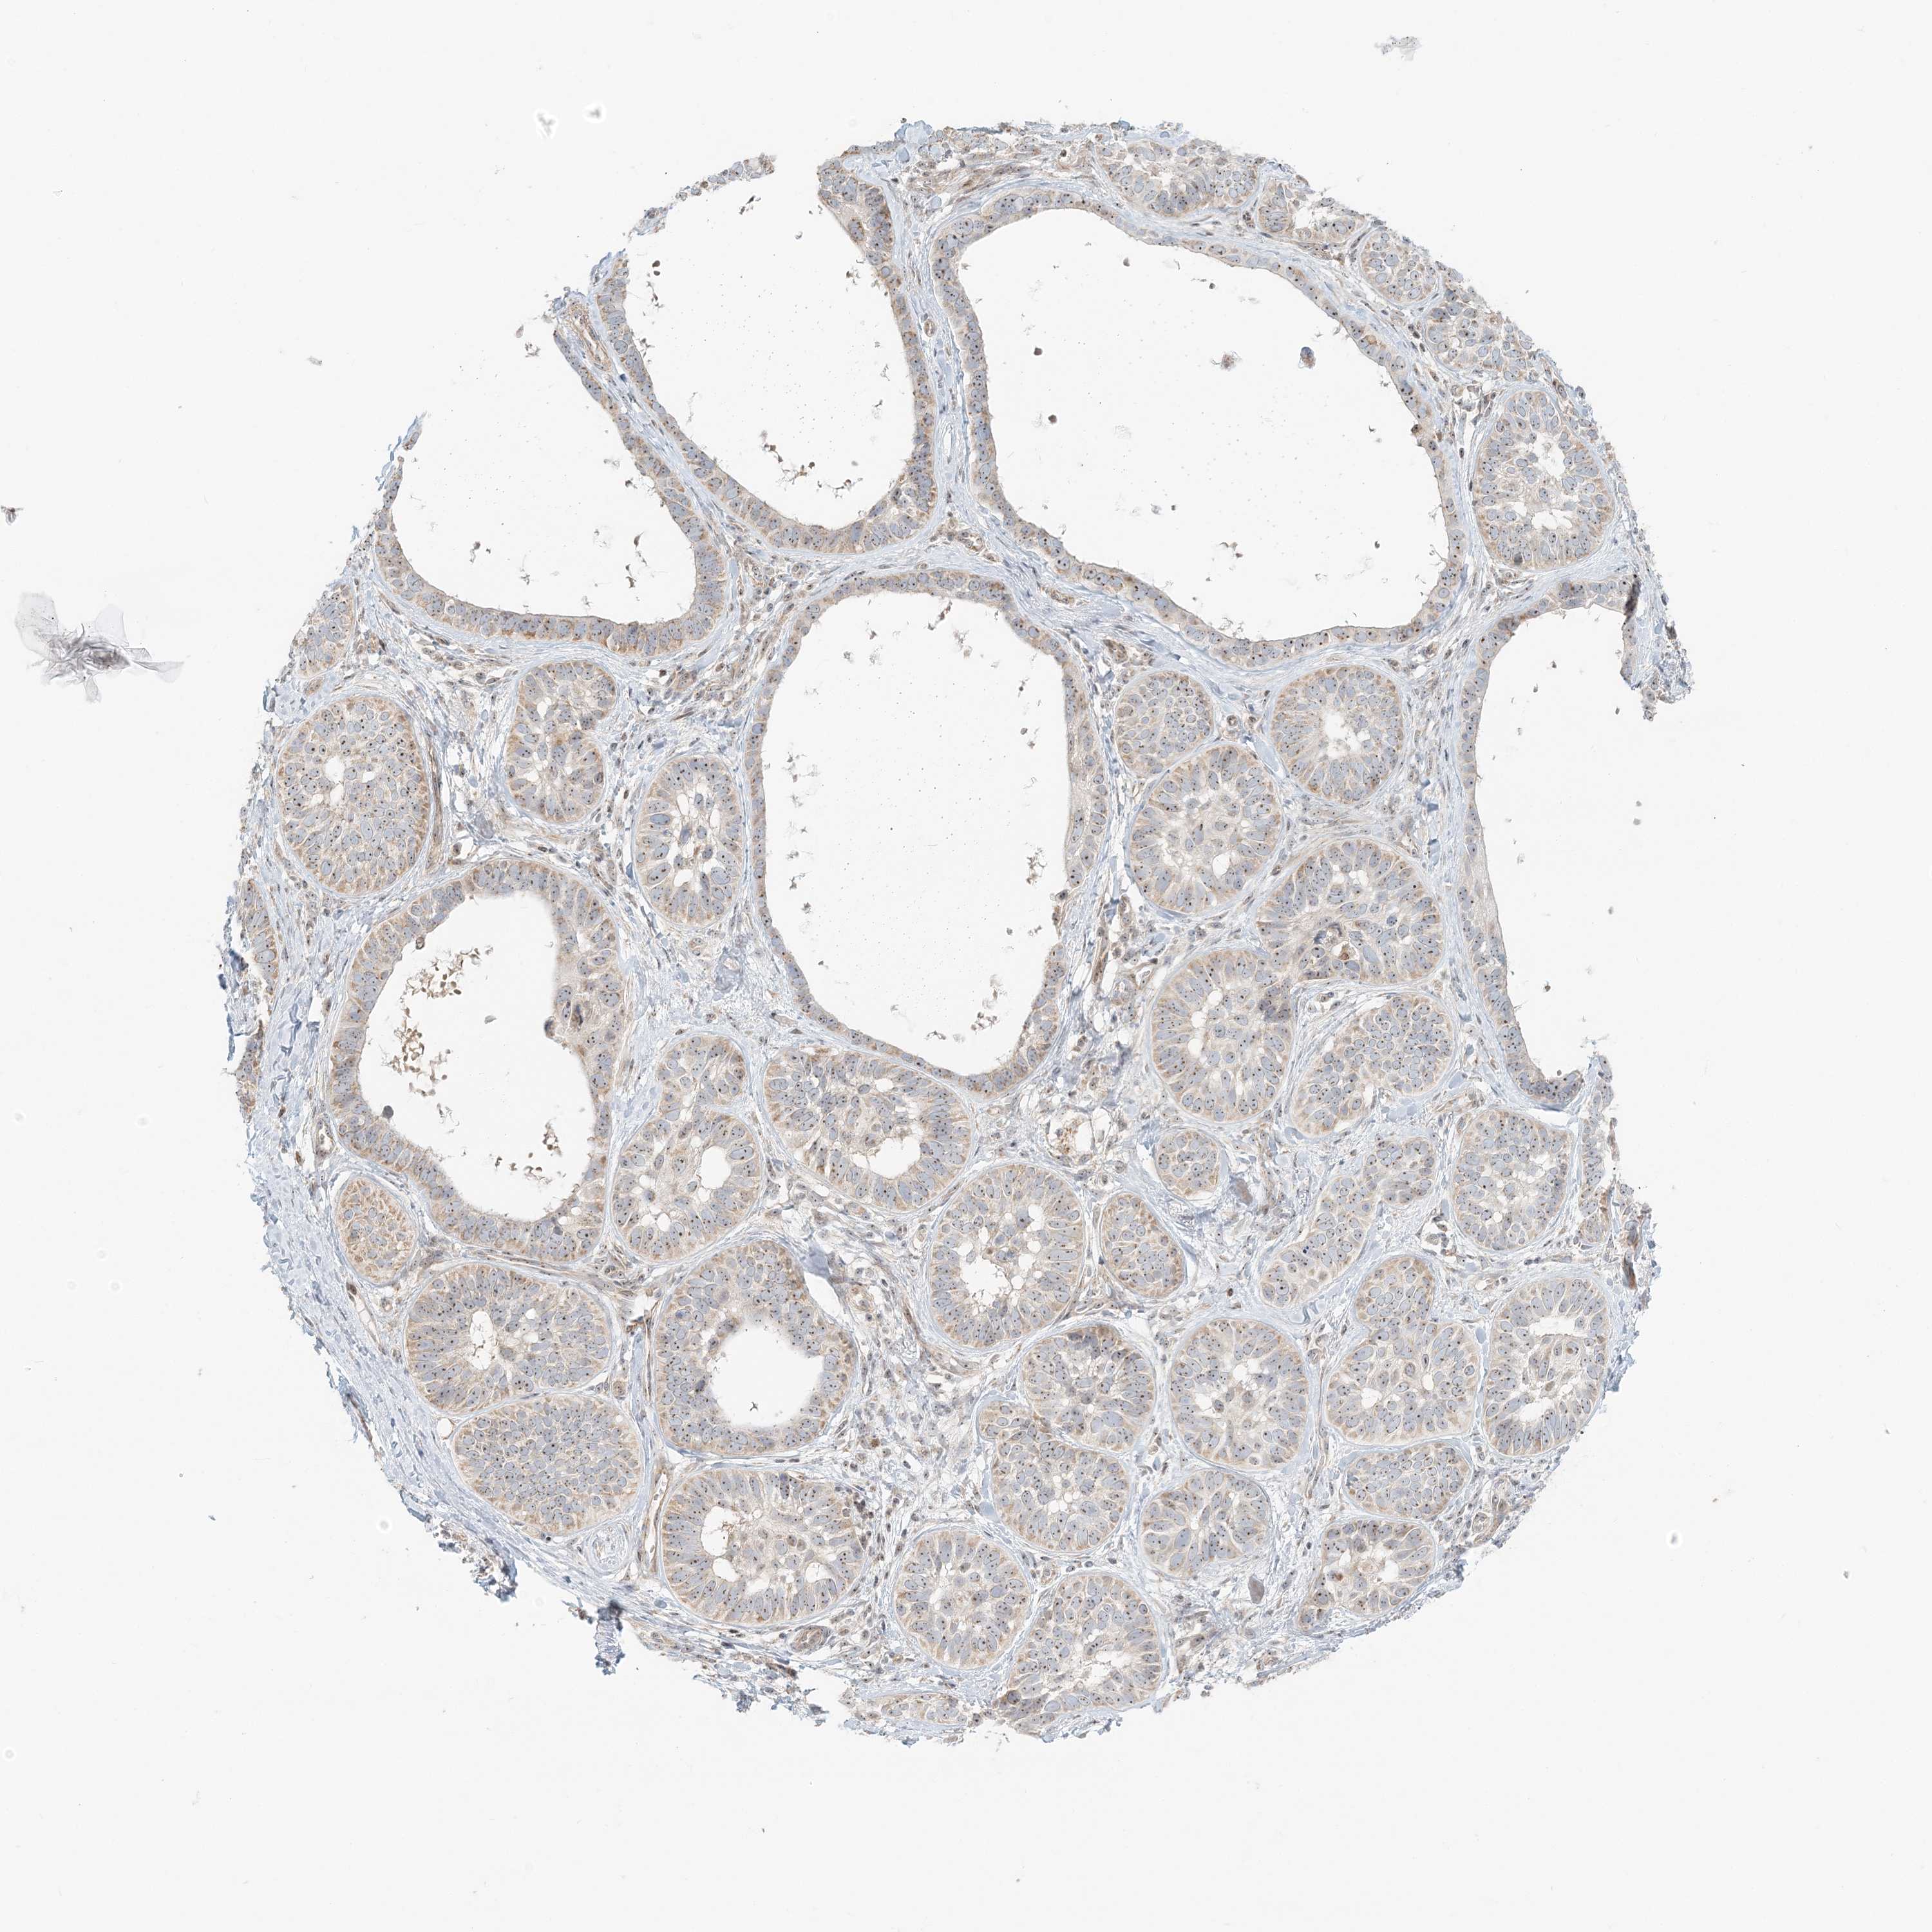

Basal cell and squamous cell cancer

SKIN CANCER - Protein expressioni

A mouse-over function shows sample information and annotation data. Click on an image to view it in a full screen mode. Samples can be filtered based on level of antibody staining by selecting one or several of the following categories: high, medium, low and not detected. The assay and annotation is described here.

Antibody stainingi

Antibody staining in the annotated cell types in the current human tissue is reported as not detected, low, medium, or high, based on conventional immunohistochemistry profiling in selected tissues. This score is based on the combination of the staining intensity and fraction of stained cells.

Each image is clickable and will lead to virtual microscopy that enables deeper exploration of all samples and also displays staining intensity scores, fraction scores and subcellular localization as well as patient and tissue information for each sample.

Antibody HPA037444

Staining

Low

Intensity

Weak

Quantity

<25%

Location

Cytoplasmic/membranous

Cytoplasmic/membranous,nuclear

Squamous cell carcinoma, NOS

Squamous cell carcinoma, metastatic, NOS